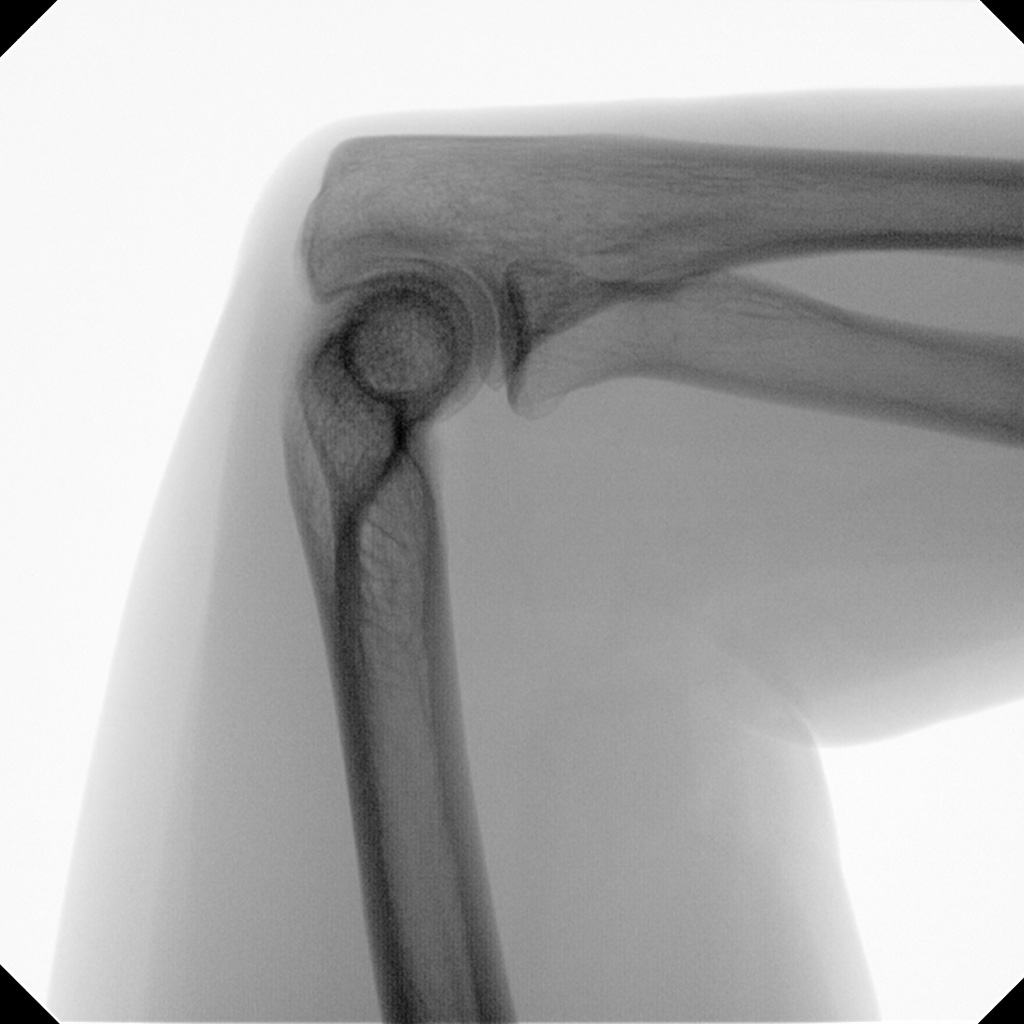

Orthopedic and trauma surgery are part of the clinical routine. From a pelvic ring fracture and stabilizing the sacroiliac joint to treating the calcaneus, intraoperative imaging using a mobile C-arm is the gold standard in the treatment of complex fractures.

The combination of a powerful generator and CMOS flat-panel technology enables significantly more distinguishable anatomies, defined bone crests, and optimum slice views without disruptive artifacts – even with obese patients.